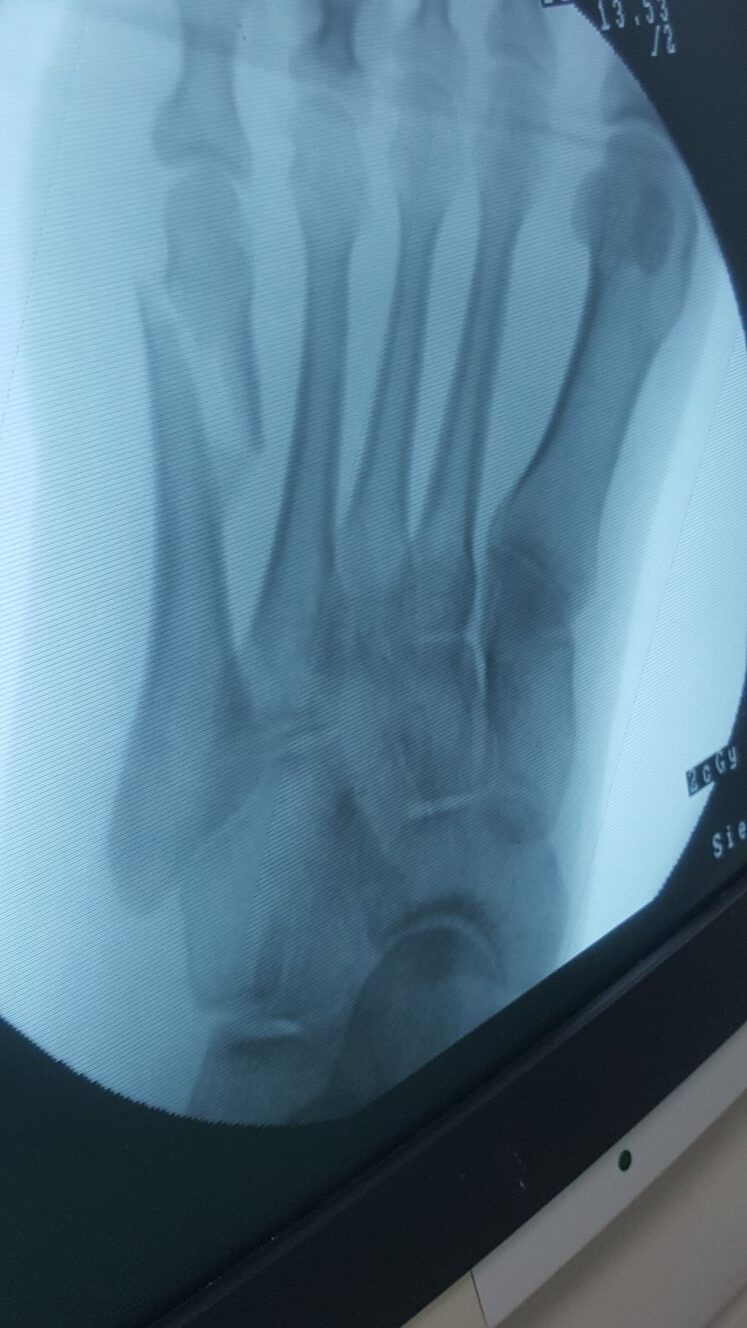

A patient receives post-fracture consultation as Dr. Imran explains bone structure using a x-ray.